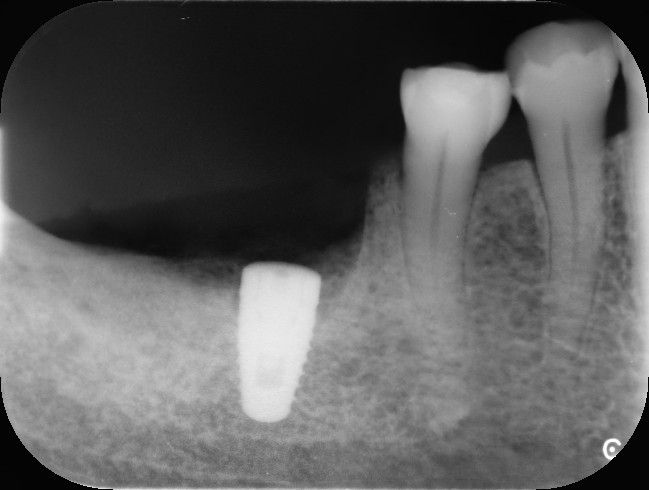

上のレントゲンの白く写っているのがインプラントです。